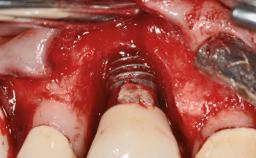

Repeated Acrylic Fractures on a Mandibular Fixed Full-arch Implant-supported Metal/Acrylic Prosthesis

A 77-year-old male patient was referred for the management of frequent and repeated acrylic fracture of his existing mandibular fixed full-arch implant-supported metal/acrylic prosthesis. He also complained about softtissue soreness and the lack of retention and stability of his maxillary removable partial metal/acrylic prosthesis. Both prostheses had been delivered two years previously as part of his full-mouth rehabilitation (caries, tooth wear, tooth fracture). His medical history revealed high blood pressure, controlled with the use of antihypertensive medication.

Type of Implants Two-Piece